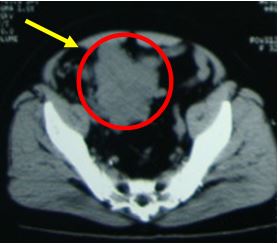

+ Bệnh nhân được tiến hành chụp cắt lớp vi tính ổ bụng để đánh giá cho thấy hình ảnh khối giảm tỷ trọng kích thước 70x90x100 mm, ranh giới rõ, bờ thùy múi, ngấm thuốc cản quang sau tiêm, trung tâm có vùng hoại tử không ngấm thuốc, khối u đè đẩy bàng quang ra sau và sang trái

Kết luận: Khối u vùng tiểu khung theo dõi lymphoma

Hình 2. Hình ảnh chụp cắt lớp vi tính ổ bụng: Khối u vùng hạ vị đè một phần vào bàng quang, đẩy bàng quang ra sau và sang trái